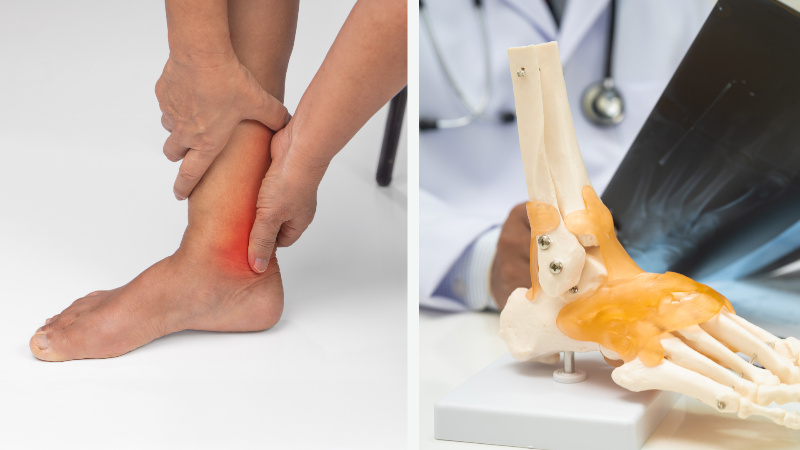

L’arthrose est une maladie chronique des articulations. Elle correspond à une dégradation du cartilage, le tissu qui permet aux os de glisser sans frottement. Avec le temps, toute l’articulation peut être touchée, y compris l’os situé dessous. Elle provoque surtout des douleurs mécaniques, une raideur, une gêne dans les mouvements et parfois une diminution de la mobilité. Elle touche souvent le genou, le gros orteil (hallux rigidus), la cheville, la hanche, les doigts ou la colonne vertébrale.

Les diagnostics de l’arthrose reposent d’abord sur l’interrogatoire et l’examen clinique : douleur mécanique arthrosique, raideur brève, gêne fonctionnelle, parfois craquements ou déformation. La radiographie confirme souvent ces diagnostics en montrant un pincement articulaire, des ostéophytes ou une atteinte osseuse. L’IRM est rarement nécessaire, sauf cas complexes. Des analyses sanguines ou une ponction articulaire peuvent être utiles surtout pour écarter d’autres causes, comme une arthrite inflammatoire ou infectieuse.

Les complications des arthrodèses près de Salon de Provence

Les complications possibles incluent l'infection, une inflammation, des saignements, des douleurs persistante, une raideur, un retard de consolidation ou pseudarthrose, déplacement ou rupture du matériel, irritation nerveuse, phlébite. Et parfois atteinte des articulations voisines à long terme.

Selon la zone opérée (pied, cheville, orteil...), il peut aussi exister un risque de lésion vasculaire, de plaie durale ou de complications inflammatoires liées à la greffe osseuse. Une surveillance postopératoire régulière est essentielle pour dépister rapidement ces problèmes et adapter le traitement avec le chirurgien et l’équipe de rééducation spécialisée.